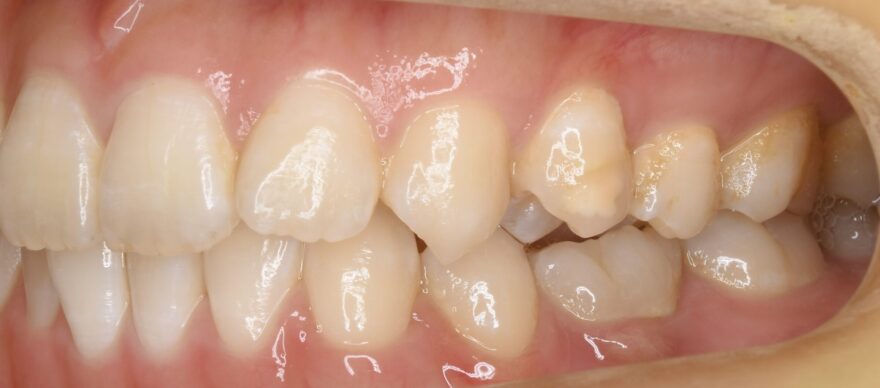

初診時の口腔内写真

この方向から見ると、前歯が出ていることが分かります。

乳歯の根本が腫れています。